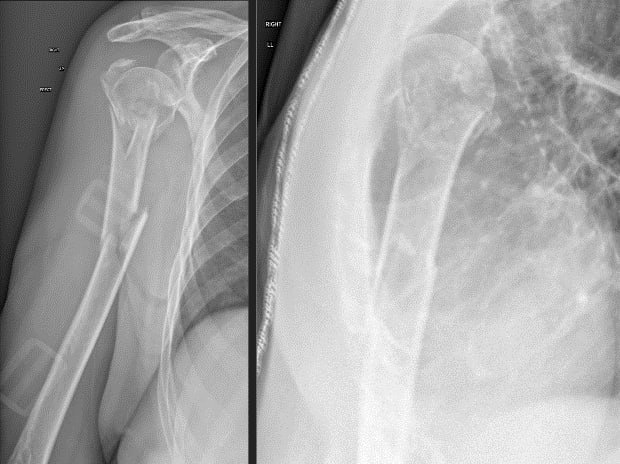

Π’ ΠΎΡ‚Π΄Π΅Π»Π΅Π½ΠΈΠ΅ экстрСнной ΠΏΠΎΠΌΠΎΡ‰ΠΈ Ильинской Π±ΠΎΠ»ΡŒΠ½ΠΈΡ†Ρ‹ ΠΎΠ±Ρ€Π°Ρ‚ΠΈΠ»Π°ΡΡŒ ΠΏΠ°Ρ†ΠΈΠ΅Π½Ρ‚ΠΊΠ° 80 Π»Π΅Ρ‚. Π‘ΠΎ слов ΠΏΠ°Ρ†ΠΈΠ΅Π½Ρ‚ΠΊΠΈ ΠΈ ΡΠΎΠΏΡ€ΠΎΠ²ΠΎΠΆΠ΄Π°ΡŽΡ‰ΠΈΡ…, Ρ‚Ρ€Π°Π²ΠΌΠ° ΠΏΠΎΠ»ΡƒΡ‡Π΅Π½Π° Π² Π±Ρ‹Ρ‚Ρƒ: ΠΏΠ°Π΄Π΅Π½ΠΈΠ΅ Π½Π° ΠΏΡ€Π°Π²Ρ‹ΠΉ Π±ΠΎΠΊ Π² Ρ€Π΅Π·ΡƒΠ»ΡŒΡ‚Π°Ρ‚Π΅ головокруТСния. ΠŸΠΎΡ‡ΡƒΠ²ΡΡ‚Π²ΠΎΠ²Π°Π»Π° Ρ€Π΅Π·ΠΊΡƒΡŽ боль, ΠΎΠ³Ρ€Π°Π½ΠΈΡ‡Π΅Π½ΠΈΠ΅ Ρ„ΡƒΠ½ΠΊΡ†ΠΈΠΈ ΠΏΡ€Π°Π²ΠΎΠΉ Π²Π΅Ρ€Ρ…Π½Π΅ΠΉ конСчности.

Π’ ΠΎΡ‚Π΄Π΅Π»Π΅Π½ΠΈΠΈ экстрСнной ΠΏΠΎΠΌΠΎΡ‰ΠΈ Ильинской Π±ΠΎΠ»ΡŒΠ½ΠΈΡ†Ρ‹ Π²Ρ‹ΠΏΠΎΠ»Π½Π΅Π½Π° рСнтгСнография ΠΏΡ€Π°Π²ΠΎΠ³ΠΎ ΠΏΠ»Π΅Ρ‡Π°, ΠΏΠΎ Ρ€Π΅Π·ΡƒΠ»ΡŒΡ‚Π°Ρ‚Π°ΠΌ ΠΊΠΎΡ‚ΠΎΡ€ΠΎΠΉ выявлСн слоТный ΠΎΡΠΊΠΎΠ»ΡŒΡ‡Π°Ρ‚Ρ‹ΠΉ ΠΏΠ΅Ρ€Π΅Π»ΠΎΠΌ хирургичСской шСйки с ΠΎΡ‚Ρ€Ρ‹Π²ΠΎΠΌ большого Π±ΡƒΠ³ΠΎΡ€ΠΊΠ°, Π° Ρ‚Π°ΠΊΠΆΠ΅ Π΄ΠΈΠ°Ρ„ΠΈΠ·Π°Ρ€Π½Ρ‹ΠΉ ΠΏΠ΅Ρ€Π΅Π»ΠΎΠΌ ΠΏΠ»Π΅Ρ‡Π΅Π²ΠΎΠΉ кости со смСщСниСм.

Учитывая возраст ΠΏΠ°Ρ†ΠΈΠ΅Π½Ρ‚ΠΊΠΈ ΠΈ Π½Π°Π»ΠΈΡ‡ΠΈΠ΅ ΡΠΎΠΏΡƒΡ‚ΡΡ‚Π²ΡƒΡŽΡ‰ΠΈΡ… Π·Π°Π±ΠΎΠ»Π΅Π²Π°Π½ΠΈΠΉ, совмСстно с ΠΏΠ°Ρ†ΠΈΠ΅Π½Ρ‚ΠΊΠΎΠΉ Π²Ρ‹Π±Ρ€Π°Π½ консСрвативный ΠΌΠ΅Ρ‚ΠΎΠ΄ лСчСния. ΠŸΠ°Ρ†ΠΈΠ΅Π½Ρ‚ΠΊΠ° Π±Ρ‹Π»Π° ΠΏΡ€ΠΎΠΈΠ½Ρ„ΠΎΡ€ΠΌΠΈΡ€ΠΎΠ²Π°Π½Π° ΠΎΠ±ΠΎ всСх Π²ΠΎΠ·ΠΌΠΎΠΆΠ½Ρ‹Ρ… ослоТнСниях ΠΏΡ€ΠΈ Π΄Π°Π½Π½ΠΎΠΌ ΠΌΠ΅Ρ‚ΠΎΠ΄Π΅ лСчСния.

ПолноС Π΄ΠΎΠ²Π΅Ρ€ΠΈΠ΅ ΠΊ Π»Π΅Ρ‡Π°Ρ‰Π΅ΠΌΡƒ Π²Ρ€Π°Ρ‡Ρƒ ΠΈ ΠΏΠΎΠ»ΠΎΠΆΠΈΡ‚Π΅Π»ΡŒΠ½Ρ‹ΠΉ настрой ΠΏΠ°Ρ†ΠΈΠ΅Π½Ρ‚ΠΊΠΈ ΠΏΡ€ΠΈΠ²Π΅Π»ΠΈ ΠΊ устойчивому ΡƒΠ΄ΠΎΠ²Π»Π΅Ρ‚Π²ΠΎΡ€ΠΈΡ‚Π΅Π»ΡŒΠ½ΠΎΠΌΡƒ Ρ€Π΅Π·ΡƒΠ»ΡŒΡ‚Π°Ρ‚Ρƒ.

Π’ настоящСС врСмя ΠΏΠ°Ρ†ΠΈΠ΅Π½Ρ‚ΠΊΠ° Π²Π΅Π΄Π΅Ρ‚ Π°ΠΊΡ‚ΠΈΠ²Π½Ρ‹ΠΉ ΠΎΠ±Ρ€Π°Π· ΠΆΠΈΠ·Π½ΠΈ: рСгулярно ΠΏΠ»Π°Π²Π°Π΅Ρ‚ Π² бассСйнС, занимаСтся скандинавской Ρ…ΠΎΠ΄ΡŒΠ±ΠΎΠΉ ΠΈ нянчит своих Π²Π½ΡƒΠΊΠΎΠ² ΠΈ ΠΏΡ€Π°Π²Π½ΡƒΠΊΠΎΠ².